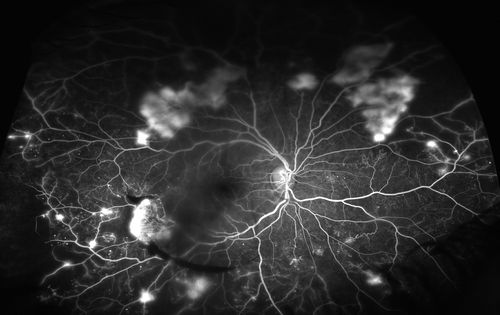

Description: Fluorescein sodium is one of the most widely used dyes in ophthalmology. It is an orange dye that fluoresces green under blue light.

- Fluorescein Angiography: Used to visualize blood flow in the retina and choroid, helping diagnose conditions like diabetic retinopathy and macular degeneration.